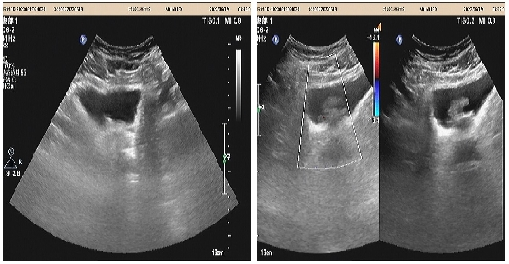

04、**女士,50岁

于2023年6月13日在邯郸仁泰东区体检,子宫附件彩超检查提示:盆腔内不规则囊实性包块,大小约21*11*10cm,以囊性为主,内见多个分隔,部分内透声差,CDFI:实性部分可见血流信号。2023年6月13日首次回访,通知客户到三甲医院进一步检查。2023年7月18日跟踪回访,客户告知,已在邯郸市中心医院东区完成肿瘤切除手术,术后恢复良好。